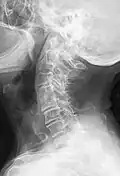

Block vertebrae occur when there is improper segmentation of the vertebrae, leading to parts of or the entire vertebrae being fused. The adjacent vertebrae fuse through their intervertebral discs and also through other intervertebral joints so that it can lead to blocking or stretching of the exiting nerve roots from that segment. It may lead to certain neurological problems depending on the severity of the block. It can increase stress on the inferior and the superior intervertebral joints. It can lead to an abnormal angle in the spine, there are certain syndromes associated with block vertebrae; for example, Klippel–Feil syndrome. The sacrum is a normal block vertebra.[8]